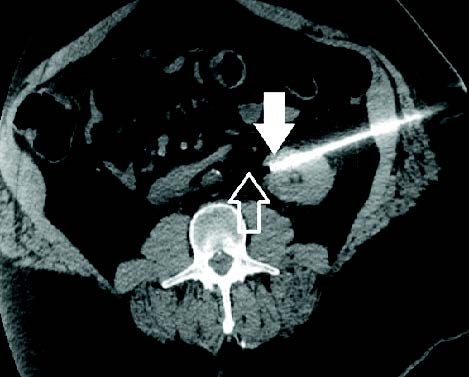

MRI image from Chary cryoneurolysis case MRI image from Chary cryoneurolysis case

Celiac Plexus Cryoneurolysis Utilized to Treat Abdominal Pain from Pancreatic Cancer

A 79-year-old man presented with abdominal pain radiating to his back. He was referred to Interventional Radiology by his Medical Oncologist for a ‘celiac plexus block.’ Two IceRod™ 1.5 CX needles were placed along the course of the celiac plexus bilaterally. The patient experienced mild orthostatic hypotension in the recovery area, a typical transient phenomenon with this treatment. The patient was seen in post-operative clinic one week after the procedure. Pain was down to 3/10 (VAS) from 8/10 (VAS) pre-op with improved appetite, better sleep, and reduced constipation. The pain relief typically last approximately 6-12 months, and the procedure can be repeated should the pain return.

Robert Evans Heithaus, MD I Vascular and Interventional Radiologist University of Florida I Gainesville, FL